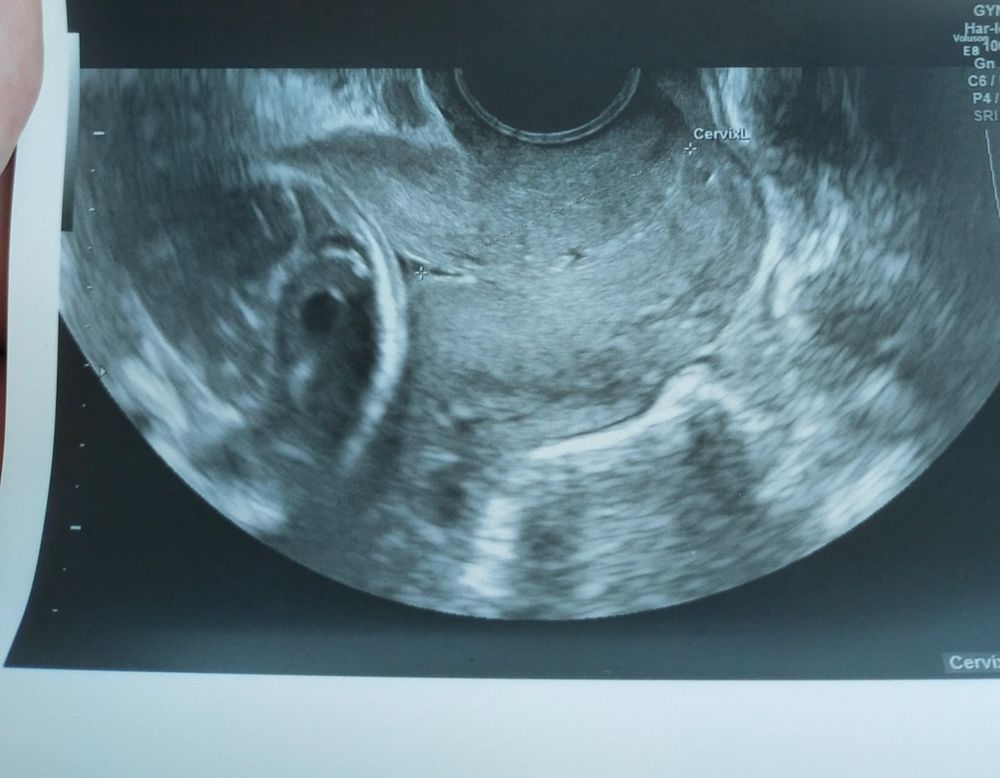

Сделали узи. Тк я ни разу не делала в кулакова. Человечек крупненький, узи ему не нравится, отворачивался. Шейка отличная - 39, зев закрыт (а галочка в области внутреннего зева только под определённым углом). Короче узист не понял зачем шить. Но врач сказала, что шейка не такая крепкая, как хотелось бы. И шить надо.